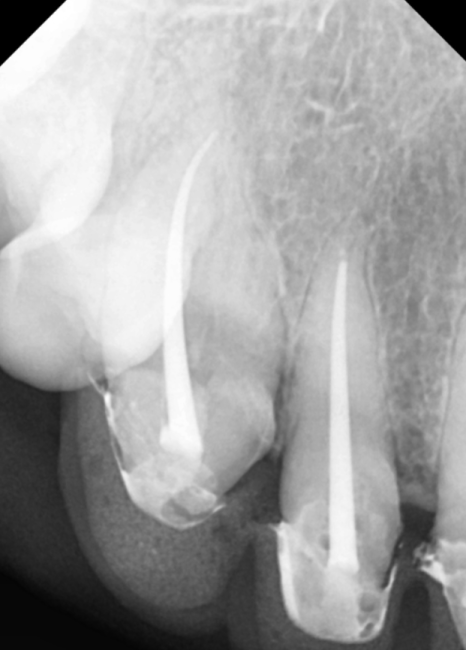

230424

이번 환자분 역시 신경이

뿌리 끝까지 제거되지 않은 상태였지만,

다행히 숨은 길을 잘 찾아내어

3번의 꼼꼼한 소독 끝에

안전하게 치료를 마무리할 수 있었습니다.

230426

신경치료 후 보철 제작을 위한

디자인 과정